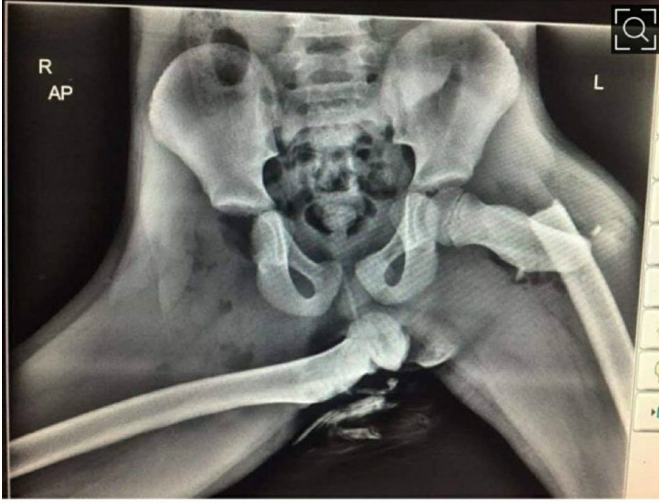

골반이 분리된 여성의 엑스레이.

사고라도 난듯 어긋난 대퇴골과 골반에서 떨어져나온 반대편 다리뼈가 찍혀있는 엑스레이 사진이다.

프라이스 경사는 트위터에 사진과 함께 “이는 충돌 당시 대시보드에 발을 올려둔 조수석 승객의 끔찍한 부상 사진”이라며 “만약 당신의 차량 탑승자가 이런 자세를 취하고 있다면 즉시 차를 세우고 이 사진을 보여달라”고 전했다.

하지만 조수석에 탑승하여 대쉬보드에 발을 올린 탑승자는 에어백 전개 여파로 코와 대퇴골, 발목 등에 심각한 부상을 입었다.

그리고 결국 완전히 탈골된 오른쪽 대퇴골로 인해 영구 장애 판정을 받았다고 한다.